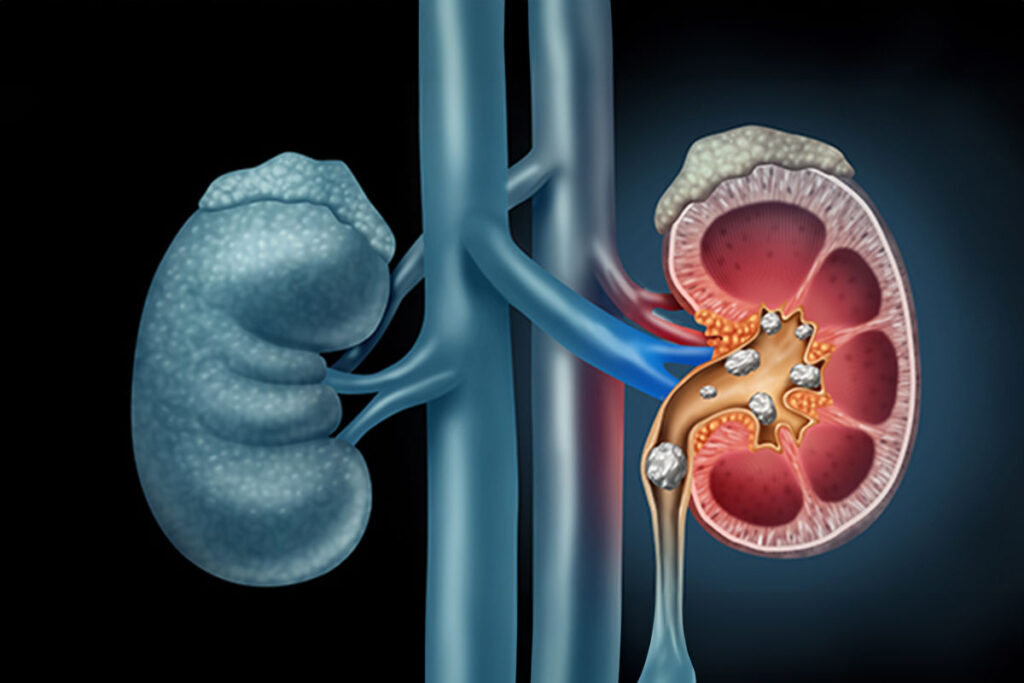

Kidney stones are small, hard deposits made of minerals and salts that form inside the kidneys. They have many causes and can affect any part of the urinary tract, from the kidneys to the bladder. Often, stones form when the urine becomes concentrated, allowing minerals to crystallize and stick together.

Kidney stones form when certain chemicals become concentrated enough in the urine to form crystals. These crystals grow into larger masses (stones), which can make their way through the urinary tract. If the stone gets stuck somewhere and blocks the flow of urine, it causes pain.